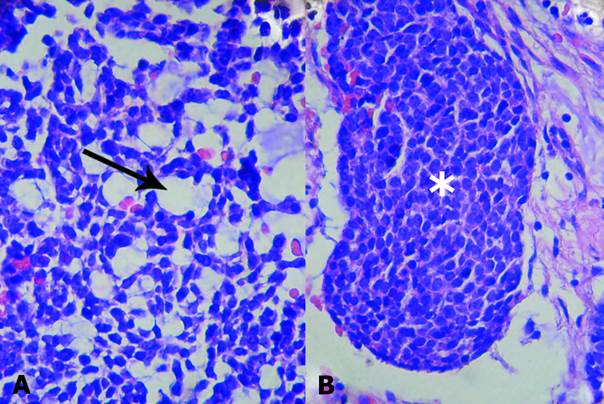

En el patrón tubular se destacaban islotes celulares basaloides que contenían seudoquistes o luces prominentes revestidos por células cuboideas (Fig. 1A y B).

El diagnóstico de adenocarcinoma de células basales tipo mixto se hizo sobre la base de sus patrones histológicos (sólido y tubular) y su carácter maligno, con un crecimiento agresivo con infiltración de la cápsula tumoral y la grasa periparotídea, invasión perineural y metástasis de un nodo linfoide regional (Fig. 2A, B y C).